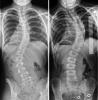

Η Schroth method είναι μέθοδος αντιμετώπισης της σκολίωσης, κύφωσης και της λόρδωσης για ανθρώπους όλων των ηλικιών, είναι επισήμως αναγνωρισμένη από τις διεθνείς επιστημονικές κοινότητες Scoliosis